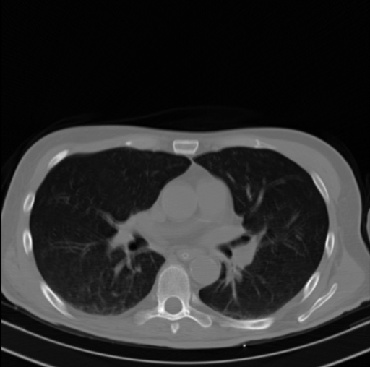

Early and reliable COVID-19 diagnosis based on chest 3-D CT scans can assist medical specialists in vital circumstances. Deep learning methodologies constitute a main approach for chest CT scan analysis and disease prediction. However, large annotated databases are necessary for developing deep learning models that are able to provide COVID-19 diagnosis across various medical environments in different countries. Due to privacy issues, publicly available COVID-19 CT datasets are highly difficult to obtain, which hinders the research and development of AI-enabled diagnosis methods of COVID-19 based on CT scans. In this paper we present the COV19-CT-DB database which is annotated for COVID-19, consisting of about 5,000 3-D CT scans, We have split the database in training, validation and test datasets. The former two datasets can be used for training and validation of machine learning models, while the latter will be used for evaluation of the developed models. We also present a deep learning approach, based on a CNN-RNN network and report its performance on the COVID19-CT-DB database.